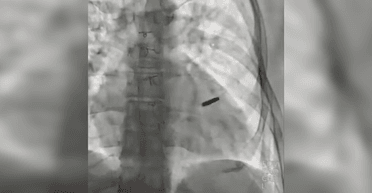

Захисника Маріуполя захопили у полон пораненим, але за три роки росіяни не провели йому операцію, щоб дістати з серця кулю. Український лікар Борис Тодуров наголосив, що українцю пощастило вижити, а тепер загроза в минулому.